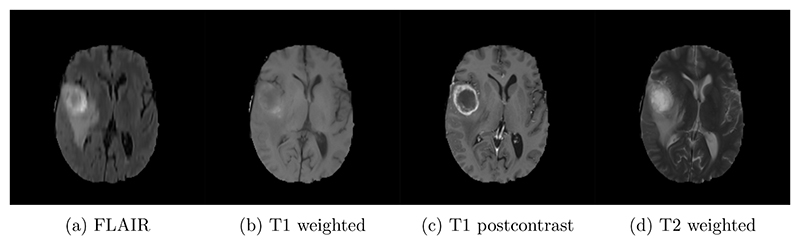

Convolutional neural networks (CNNs) allow for parameter sharing and translational equivariance by using convolutional kernels in their linear layers. By restricting these kernels to be SO(3)-steerable, CNNs can further improve parameter sharing. These rotationally-equivariant convolutional layers have several advantages over standard convolutional layers, including increased robustness to unseen poses, smaller network size, and improved sample efficiency. Despite this, most segmentation networks used in medical image analysis continue to rely on standard convolutional kernels. In this paper, we present a new family of segmentation networks that use equivariant voxel convolutions based on spherical harmonics. These networks are robust to data poses not seen during training, and do not require rotation-based data augmentation during training. In addition, we demonstrate improved segmentation performance in MRI brain tumor and healthy brain structure segmentation tasks, with enhanced robustness to reduced amounts of training data and improved parameter efficiency. Code to reproduce our results, and to implement the equivariant segmentation networks for other tasks is available at http://github.com/SCAN-NRAD/e3nn_Unet.